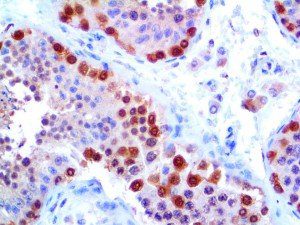

The first cytokines released are interleukin 1β (IL-1β) and tumor necrosis factor-α (TNF-α), which attract a variety of circulating white blood cells (WBCs) to the infection site, including neutrophils, monocytes, macrophages, and natural killer (NK) cells. This response, along with the antipathogenic chemicals released by these cells (i.e., complement), comprise the innate immune response. These cells directly attack the invading pathogen and also release additional cytokines, chief among them interleukin-1 and 6 (IL-6). IL-6 is essential for invoking the adaptive immune response, which calls T-cells, B-cells, and T helper (Th) cells to the infection site. IL-6 also stimulates further recruitment, proliferation and activation of macrophages.

It is the ICU physician who is most likely to witness one of the deadliest manifestations of the abnormal immunological response, the cytokine storm syndrome (CSS). This response is also referred to by some as the cytokine release syndrome (CRS). CSS is characterized by continuous activation and expansion of macrophage and lymphocyte populations, which secrete large amounts of cytokines, causing the cytokine storm. This massive cytokine release is akin to hemophagocytic lymphohistiocytosis (HLH) disease, a syndrome characterized by initial unchecked and persistent activation of cytotoxic T lymphocytes and NK cells.

This activation induces inflammatory monocytes to highly express IL-6, starting a localized and then systemic cascade effect that results in hyperproduction of IL-6, which accelerates the inflammatory process. Because IL-6 also increases vascular permeability, excessive levels cause blood vessels to become very leaky. This, along with clotting factors released from vascular endothelial cells, stimulates the coagulation cascade, resulting in microthrombosis (tiny clots), which leads to ischemia and tissue death of the kidney, intestines, heart, liver, brain and extremities.